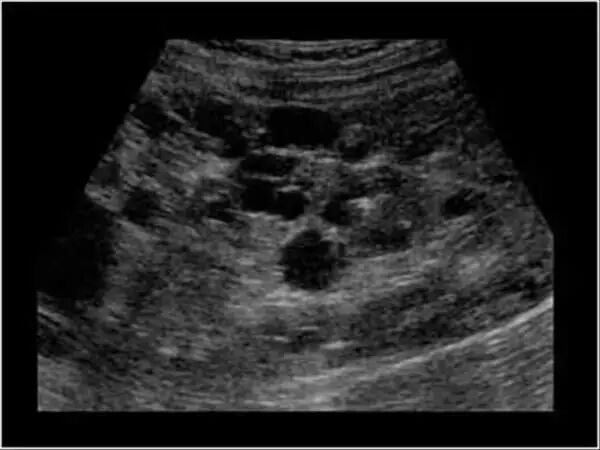

多囊肾(PKD)是一种历史悠久的遗传病。这种遗传病不仅人类会患上,猫咪也逃不过。患病猫的肾脏中出现充满液体的包囊不断增大挤压正常肾脏结构,慢慢导致肾脏机能不足最终衰竭。

一般来说,患猫到中年(5-7岁)之后,肾脏功能才受到可察觉的影响,出现机能不足。

它是一种缓慢发展的遗传性肾病,主要遗传长毛猫,其中波斯猫已被证实为通过单一显性遗传基因遗传给子代波斯猫。

也常见于其它品种如喜马拉雅猫、英国短毛猫、美国短毛猫、布偶猫、苏格兰折耳猫等。